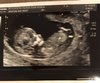

Czesc kochane, u mnie tez juz po wizycie, baby mieciu machal raczka jak tylko wlaczylismy usg, wszystko jest ok, robili prenatalne, przeziernosc karkowa i budowa w porzadku wiec moge troche odetchnac. Dzis dokladnie 12 tydzien, termin na 15 kwietnia [emoji173]️[emoji173]️.Zobacz załącznik 903556

• IMG_1242.JPG